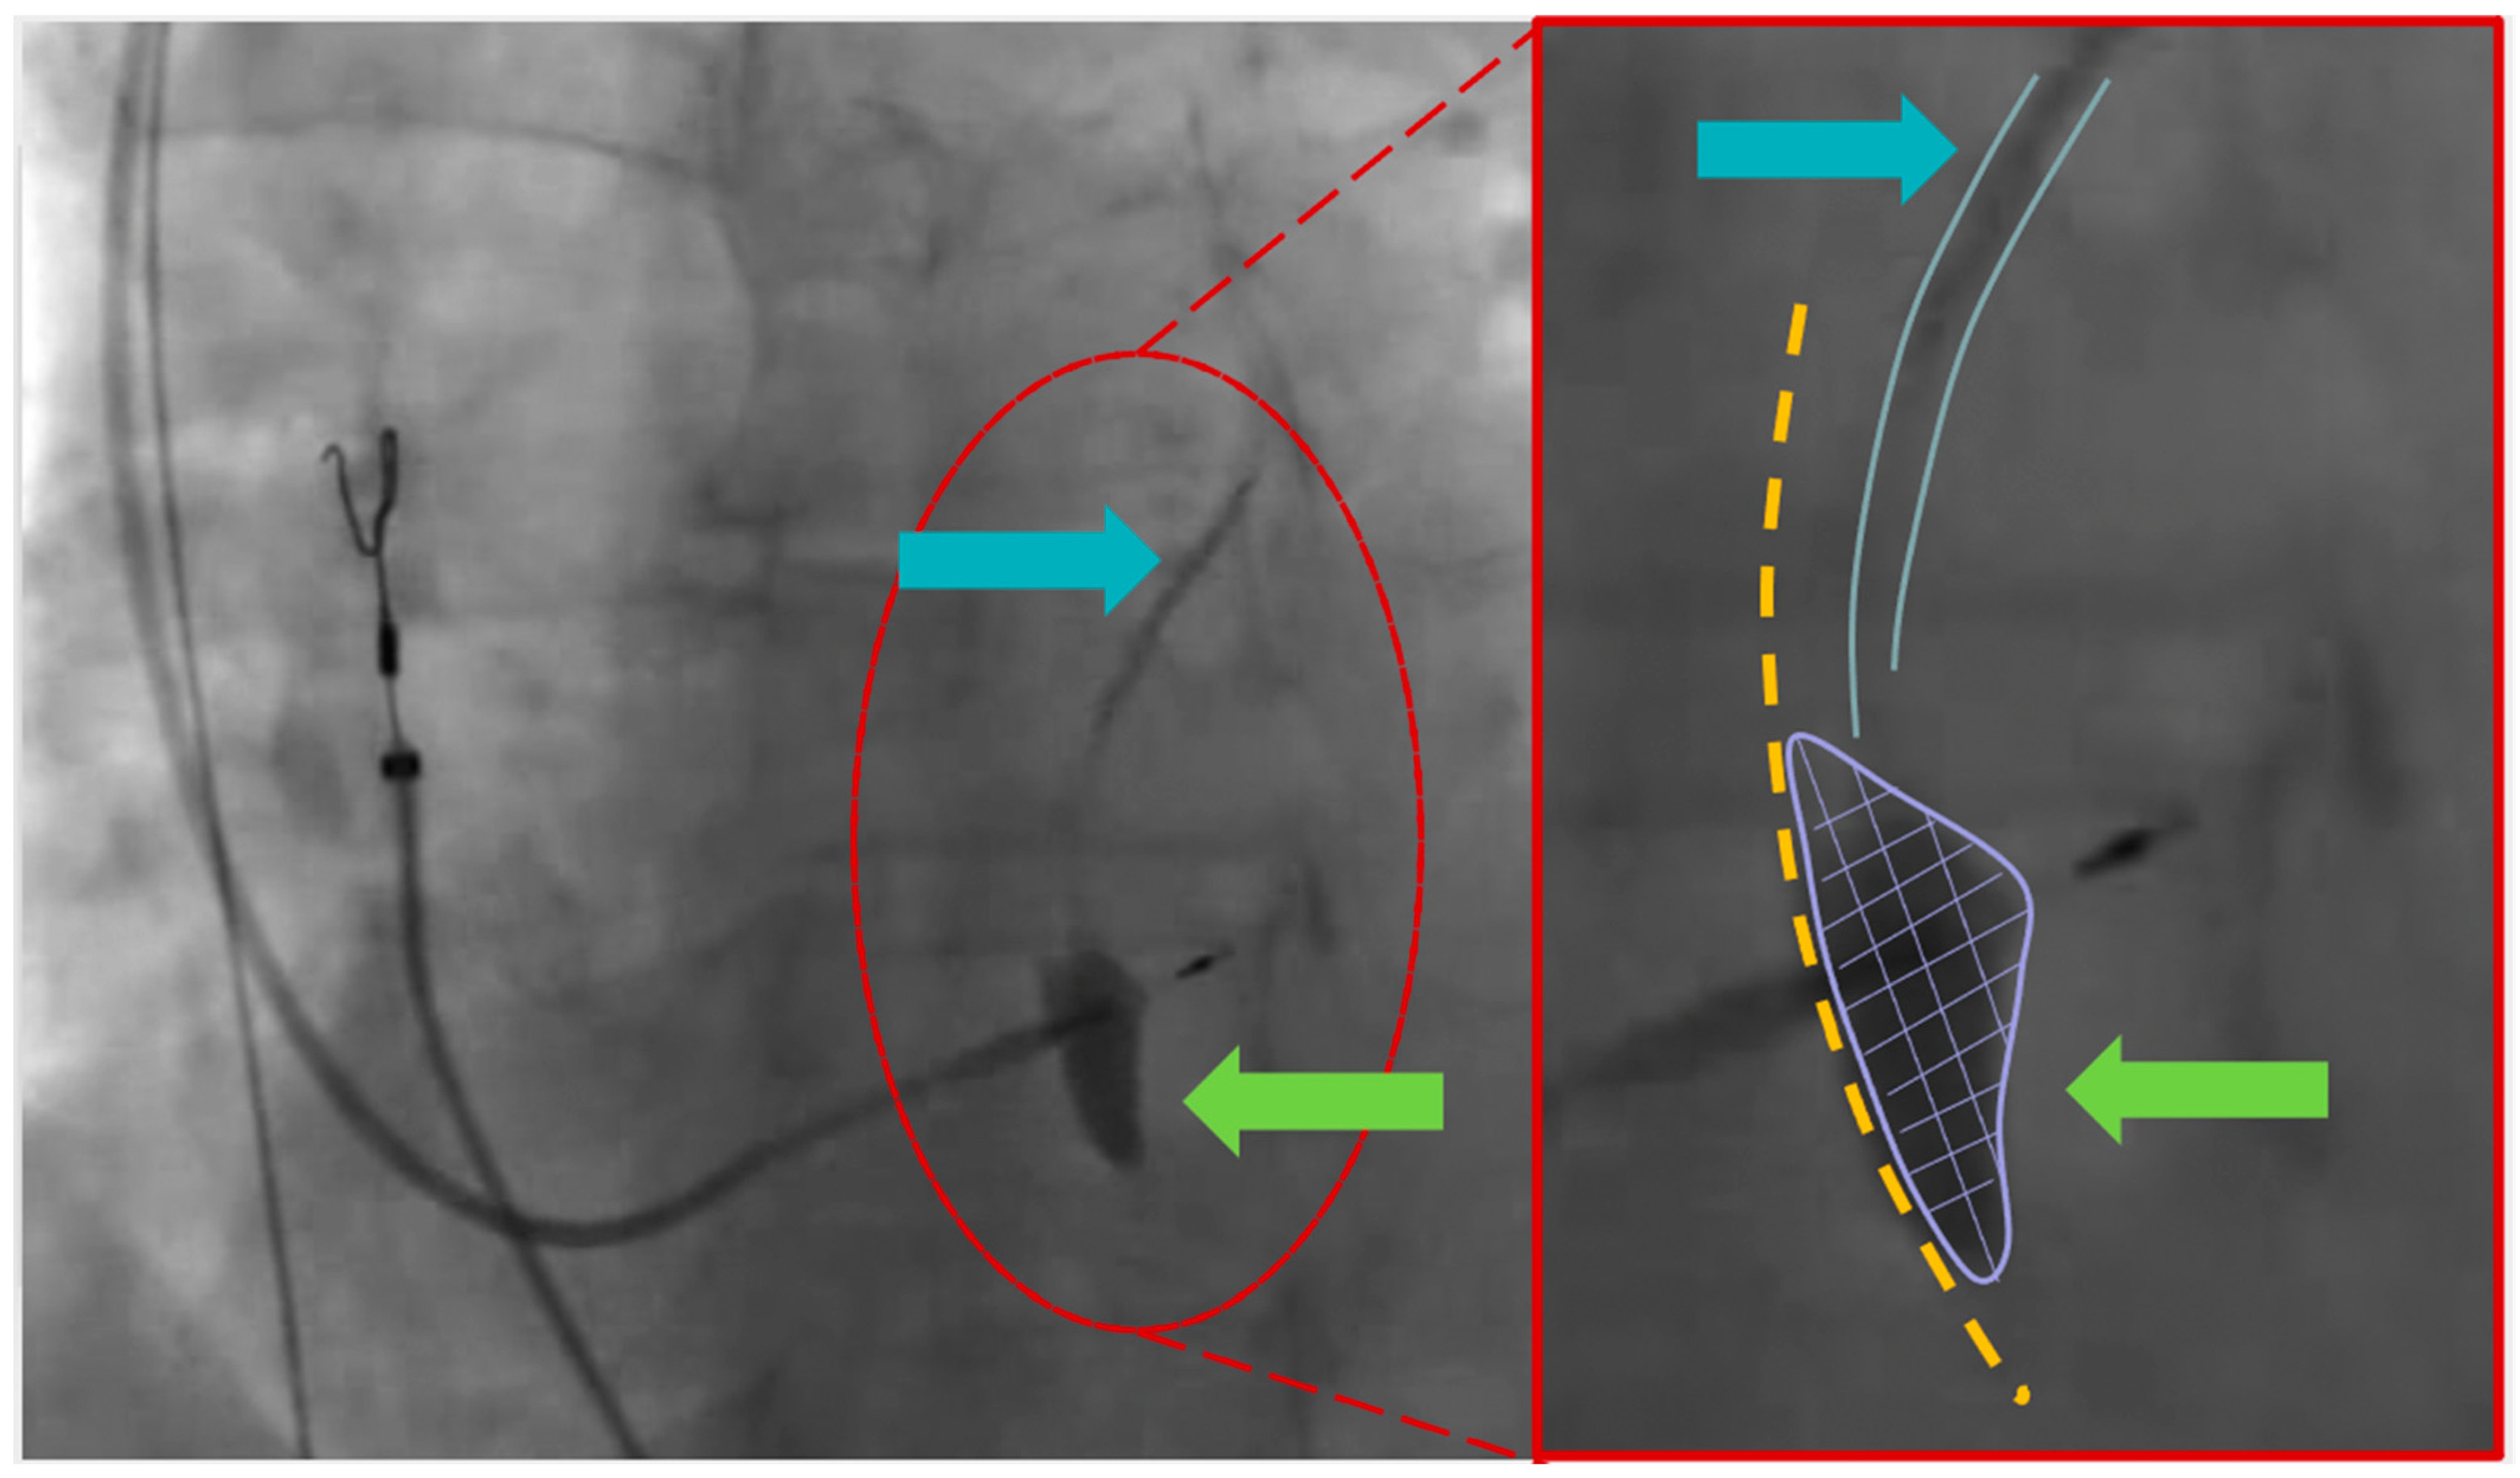

Figure 1.

Left part (left anterior oblique view—35°): The image displays the second positioning attempt of the ventricular lead. The green arrow indicates the observed stagnation of contrast inside the septum. The light blue arrow highlights the septal branch. Right part (enlarged image): The right part of the interventricular septum is marked with a yellow dot line. The green arrow and purple line emphasize the stagnation of contrast directly linked to the septal branch (depicted by the light blue lines and arrow).